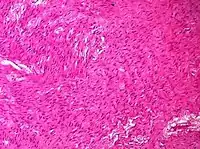

| Sex cord-stromal tumor | Ovarian fibroma | 1.5% | 0% | Spindle-shaped fibroblastic cells and abundant collagen.[8] |  |